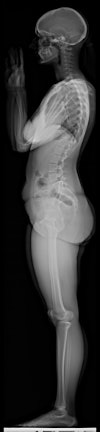

| EOS can scan the entire body in a single study. |

That theory was put to the test in a study of 50 pediatric patients referred for spine radiography to diagnose suspected scoliosis. The study, led by Sylvain Deschênes, Ph.D., of Sainte-Justine Mother and Child University Hospital Center in Montreal, was presented at this week's Journées Françaises de Radiologie (JFR) meeting in Paris.

The researchers used the EOS system on 39 female and 11 male patients with an average age of 14.8 years (± 3.6 years). Patients first received an EOS scan, followed by a CR study (FCR7501S, Fujifilm Medical Systems, Tokyo). In addition to measuring radiation dose, the researchers also assessed the image quality of the EOS system relative to CR.

The study protocol consisted of posterior-anterior and sagittal views of the spine, and images were taken so at least the last cervical vertebra and pelvis were visible. Dosimeters were placed on the skin of each patient to record x-ray dose, and dose for both the EOS system and the CR unit were recorded at seven different locations, ranging from the nape of the neck to the distal iliac crest. Radiation dose was as follows: